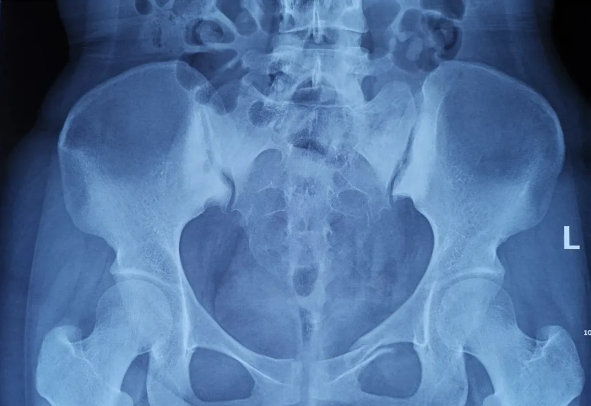

2025-02-28智匯天璣|高齡不是禁區(qū)!北京積水潭醫(yī)院智能骨科機器人助力90歲骨盆骨折患者重獲行走

由北京積水潭醫(yī)院院長蔣協(xié)遠(yuǎn)、智能骨科研究型病房主任王軍強帶領(lǐng)的智能骨科團隊,運用骨科機器人輔助經(jīng)皮骨盆通道螺釘置入技術(shù),成功救治了一名90歲高齡的骨盆骨折患者。 -

2021-01-06天璣骨科手術(shù)機器人落戶南昌市第一醫(yī)院,助力骨盆骨折閉合復(fù)位內(nèi)固定術(shù)順利完成

近日,天璣?骨科手術(shù)機器人落戶南昌市第一醫(yī)院,助力骨盆骨折閉合復(fù)位內(nèi)固定術(shù)順利完成。作為江西省首先采用5G引導(dǎo)下的骨科機器人手術(shù),天璣?骨科手術(shù)機器人用它的“透視眼”,以三維影像掃描進(jìn)行深層三維空間精準(zhǔn)定位,為患者“量身定做”了最理想、最安全的教科書般通道,完成了復(fù)雜骨盆骨折微創(chuàng)治療一次性完美置釘及腰椎骨折微創(chuàng)經(jīng)皮置釘?shù)氖仔悖蔀榻魇」强瓢l(fā)展的標(biāo)志性事件,同時也是江西省骨科步入新型數(shù)字智慧骨科時代的重要里程碑事件。 -